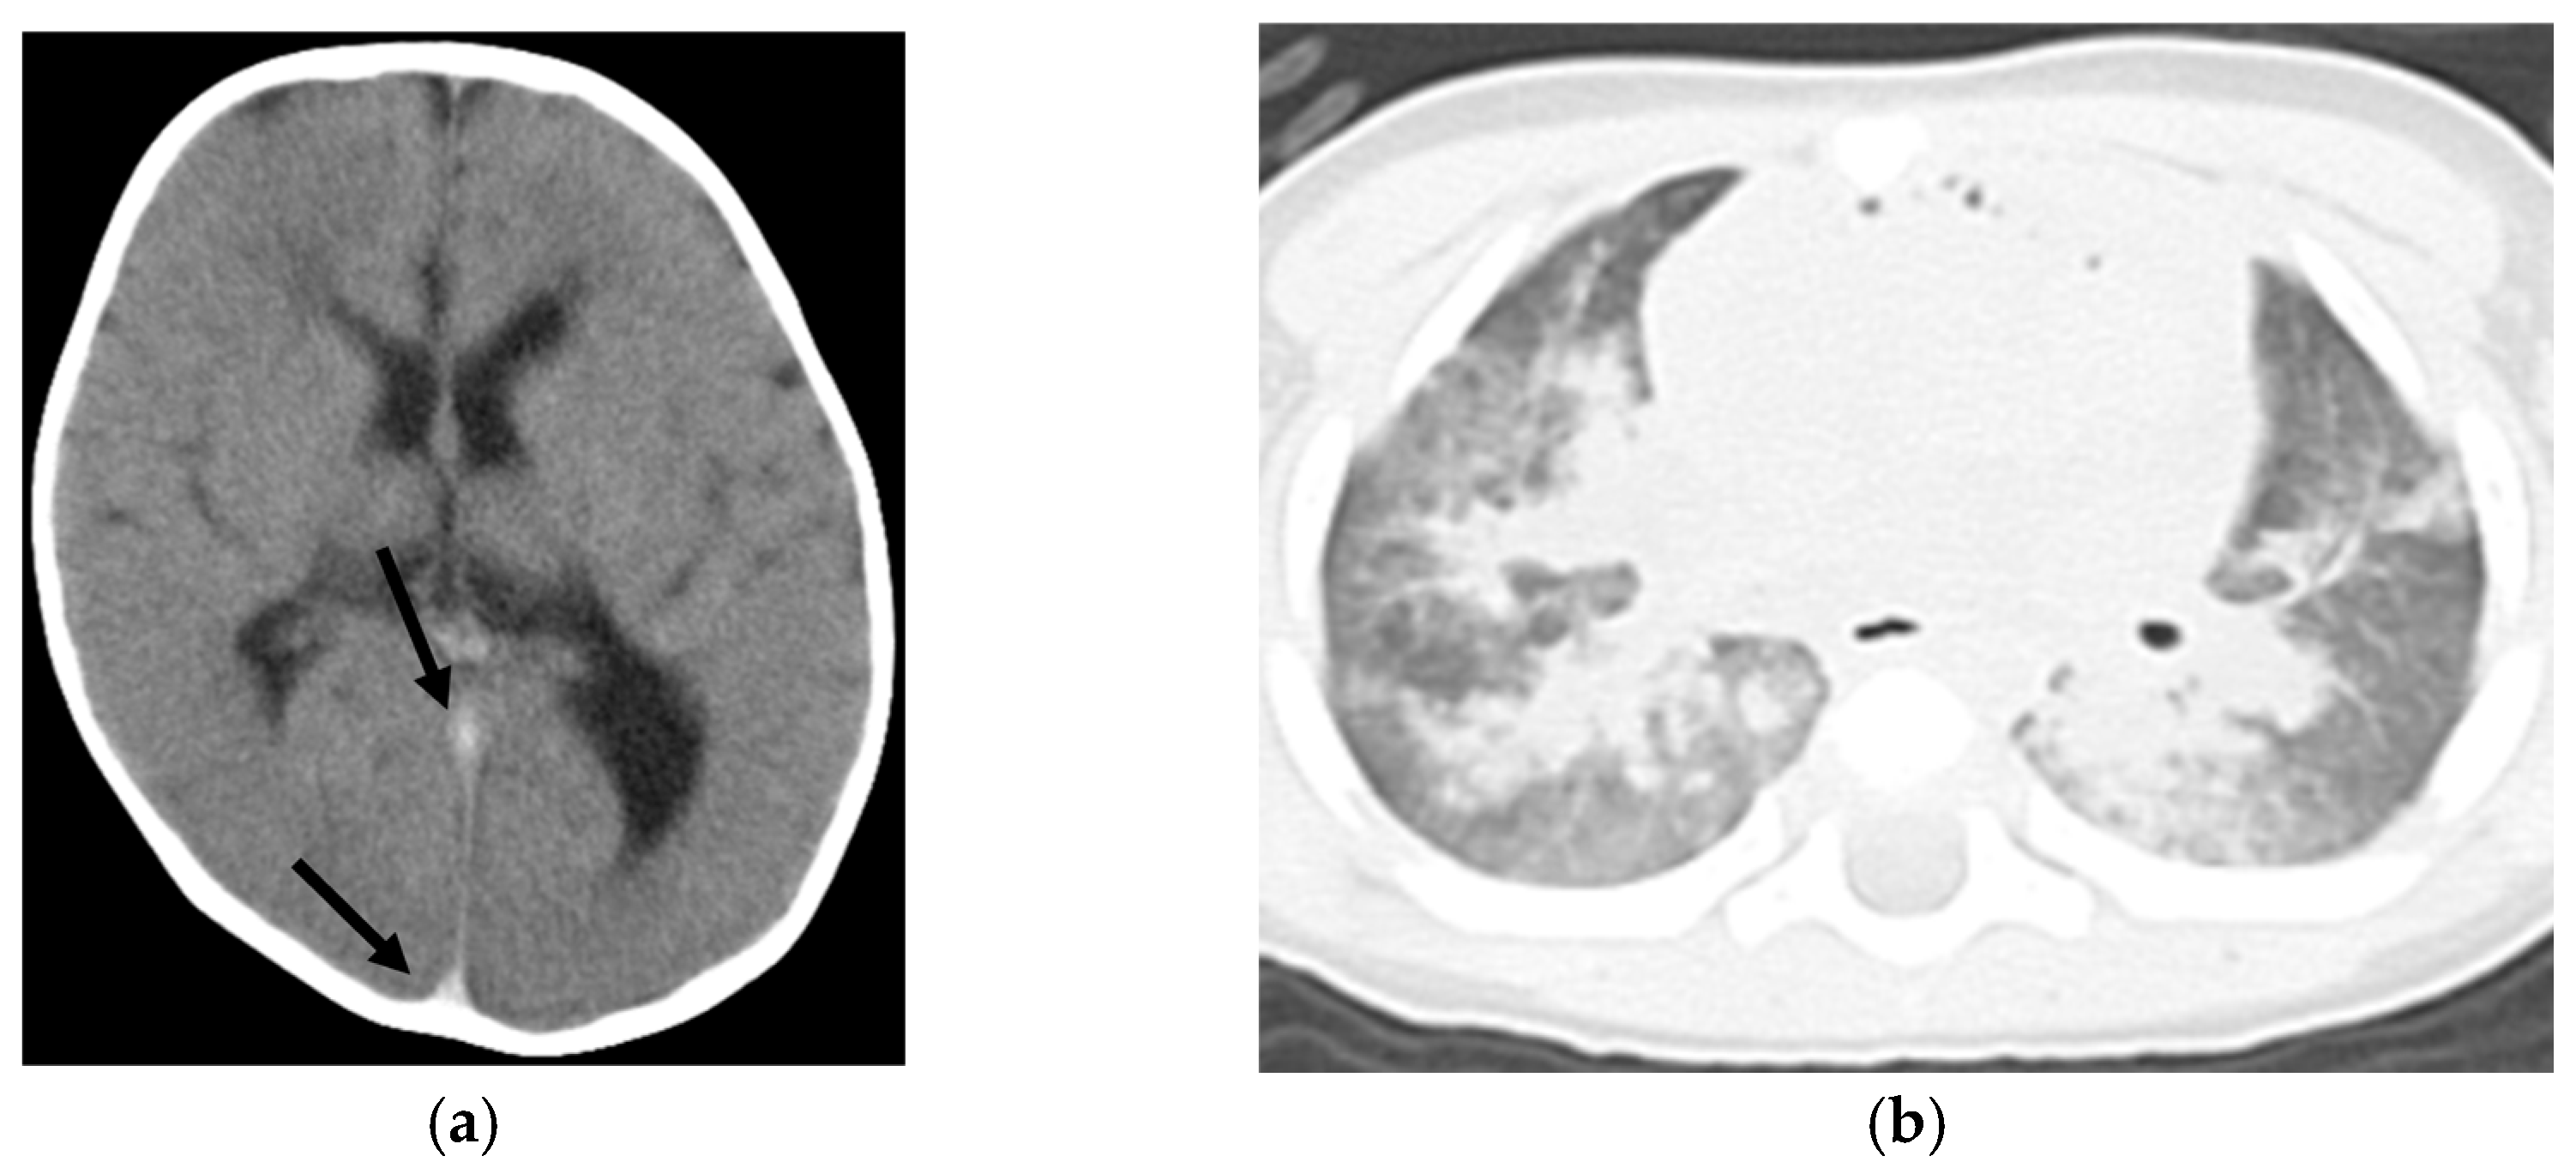

| Brain swelling | 16 | 1 | <0.001 |

| Loss of cerebral gray-white matter differentiation | 14 | 3 | 0.033 |

| Symmetrical consolidation/ground-glass opacity | 18 | 4 | 0.017 |